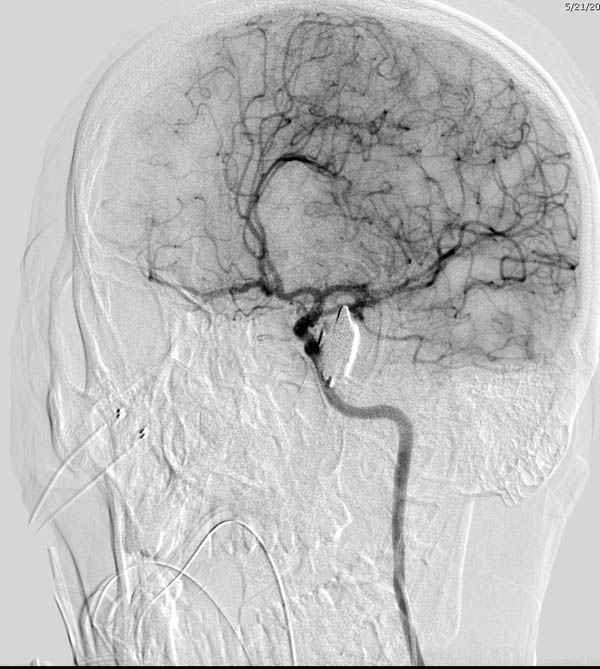

В своих выступлениях я рассказывал, что наши центры в мирное время по пенетрирующим травмам не уступает Ираку или Афганстану, и вот недавно к нам поступила больная 22 лет, травма "ножом в глаз" от бывшей подруги нынешнего "бой френда".

При поступлении в сознании, жаловалась на неприятные ощущения в глазнице.

По протоколу сделаны все необходимые исследования: рентген, ангиограмма с 3Д реконструкцией, где обнаружили что все жизненно важные сосуды не задеты, даже некоторые "сидят" изгибаясь на ноже.